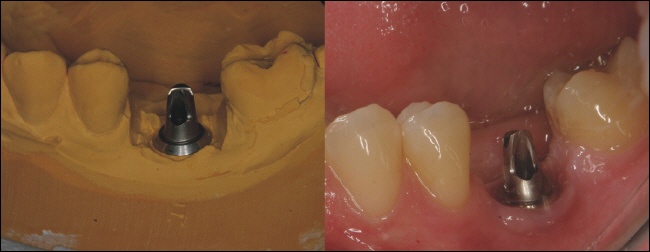

Implantataufbau

Nach der Einheilung des Implantates wird ein individueller Aufbau für das Implantat im Zahnlabor hergestellt. Man sieht den Aufbau links auf dem Gipsmodell des Zahntechnikers und rechts eingeschraubt auf das Implantat.

Auf diesen Aufbau wird die fertige Krone zementiert.